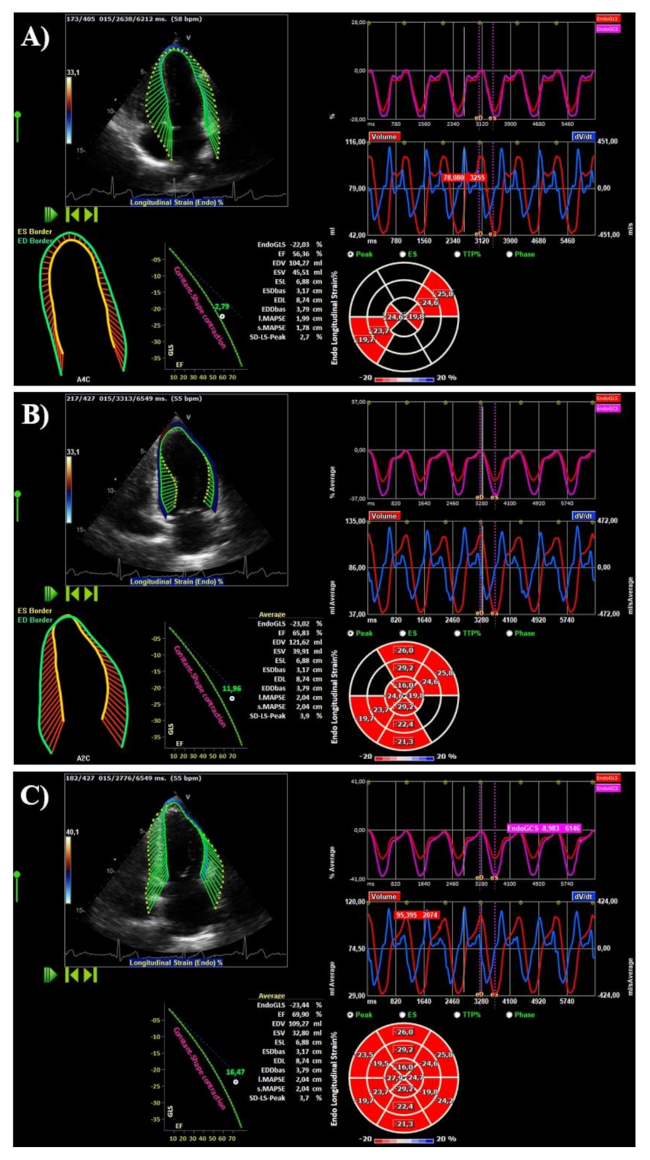

2.3. Speckle-Tracking Analysis

2.4. Hemodynamic Forces

3.4. LV Deformation

3.5. LV Hemodynamic Forces